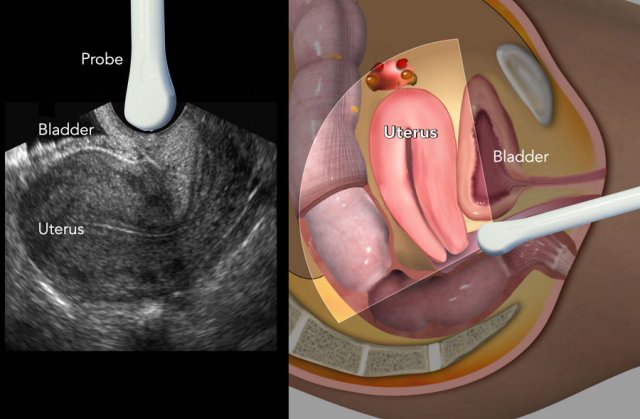

Chelyabinsk viloyat kasalxonasida transvaginal ultratovush tekshiruvi